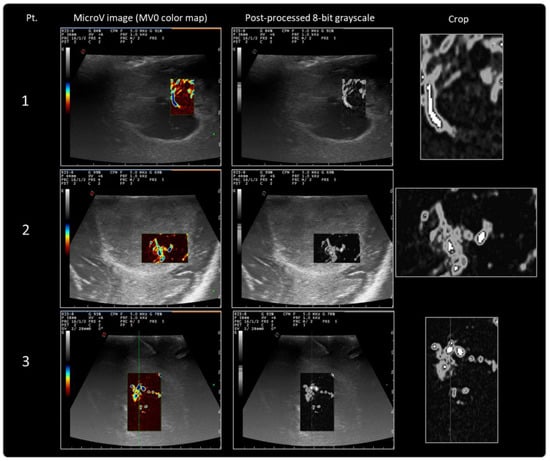

| Pt. | Histology | Location | N. | Area (px2) | Mean | StDev | Min | Max | Mode |

|---|---|---|---|---|---|---|---|---|---|

| F, 68 y | GBM | Lt. frontal | 13,775 | 964.309.787.326 | 53.884 | 56.996 | 0 | 254 | 8 (645) |

| M, 57 y | GBM | Rt. frontal | 21,879 | 1.531.624.960.938 | 33.741 | 48.799 | 0 | 254 | 8 (6849) |

| M, 71 y | GBM | Lt. temporo-parieto-occipital | 30,989 | 2.169.364.500.868 | 27.887 | 42.783 | 0 | 254 | 8 (3651) |

| F, 66 y | GBM | Rt. parietal | 36,816 | 2.577.279.791.667 | 11.529 | 19.424 | 0 | 190 | 8 (32676) |

| F, 62 y | GBM | Rt. frontal | 25,252 | 1.767.749.600.694 | 12.075 | 14.387 | 0 | 174 | 8 (10259) |

| M, 67 y | GBM | Rt. temporal | 35,412 | 2.478.993.697.917 | 56.478 | 67.567 | 0 | 254 | 254 (2644) |

| F, 45 y | GBM | IV ventricle | 10,998 | 769.907.734.375 | 18.649 | 27.067 | 0 | 254 | 8 (3617) |

| F, 62 y | GBM | Lt. temporal | 6102 | 427.166.484.375 | 31.701 | 15.528 | 0 | 180 | 28 (401) |